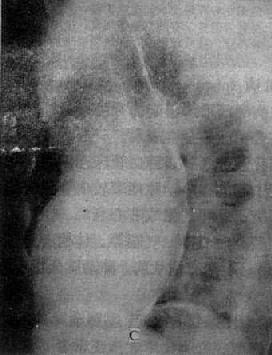

图3-2-15 二尖瓣狭窄

A.右前斜位:右心室增大,肺动脉段突出(↑),心前间隙变窄(↑),左心房轻度增大;B.后前位:心增大,呈二尖瓣型,右心室增大,肺动脉段突出,左心耳增大,出现第三弓(↓),有肺瘀血表现;C.左前斜位:右心室增大,左心房增大不明显;左心室不增大。